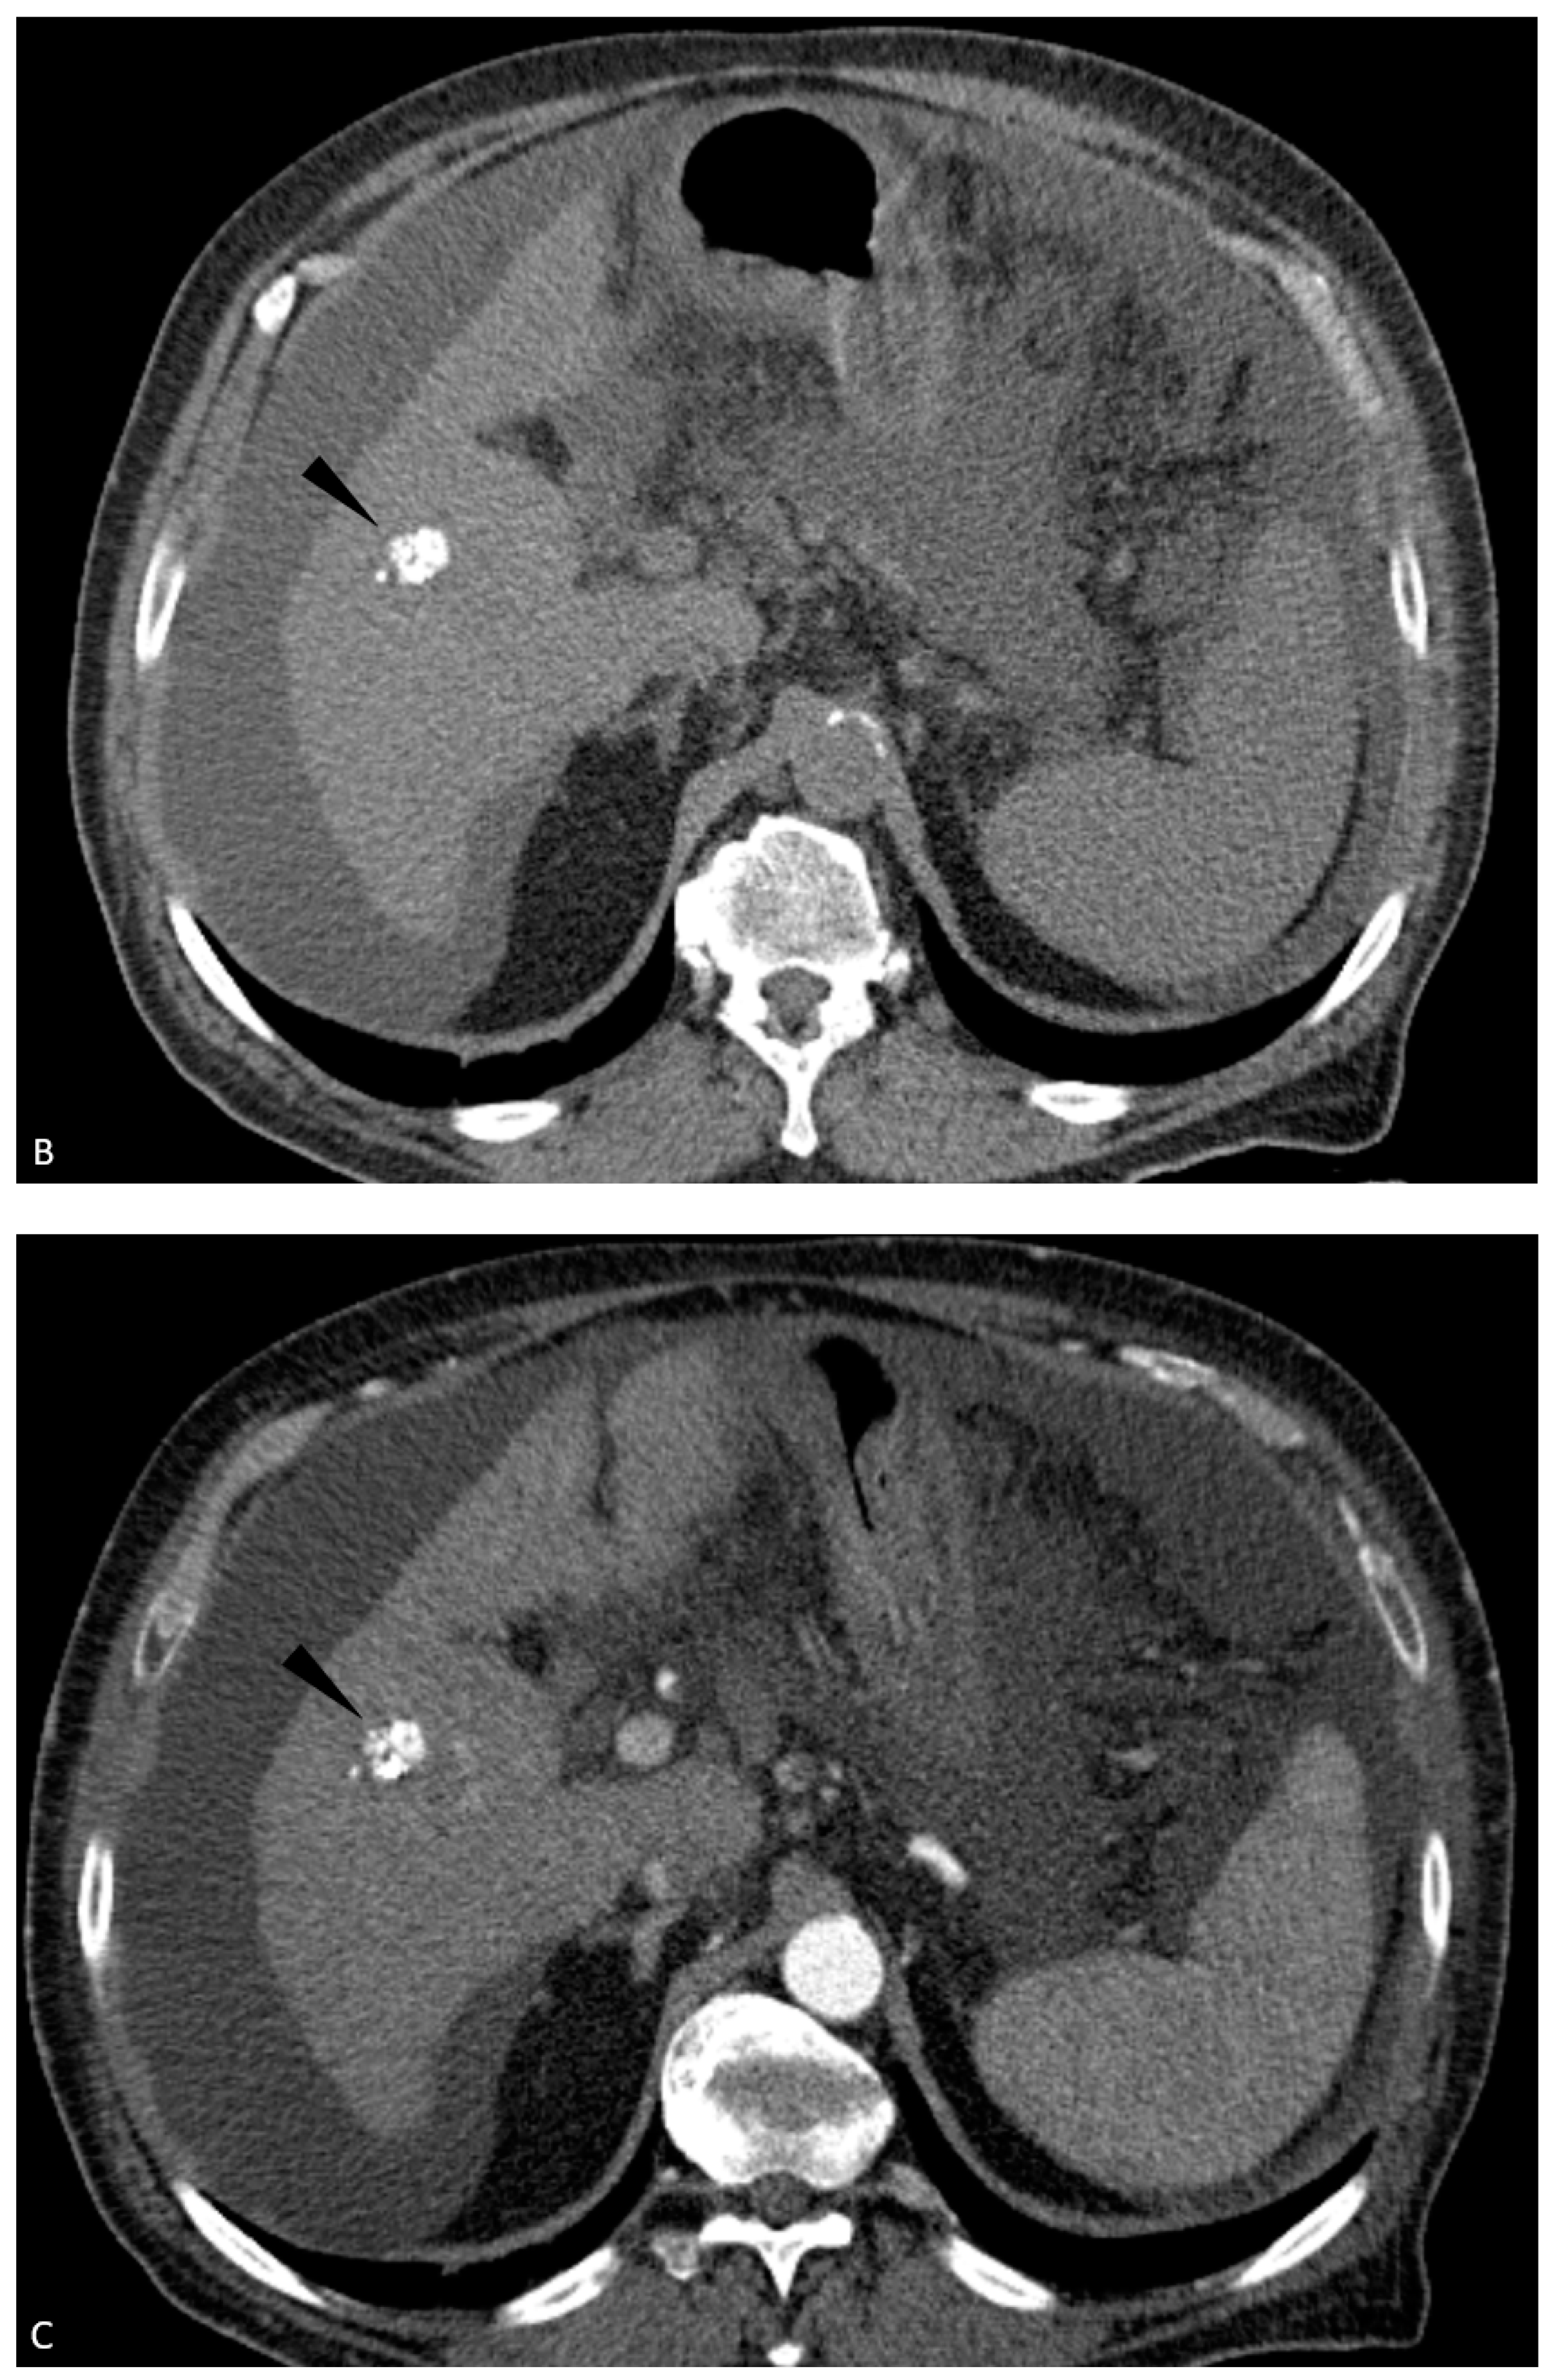

| 6 | CEUS | Target | LR-viable | CT missed subtle disease at the periphery of the treated HCC (Figure 2) |